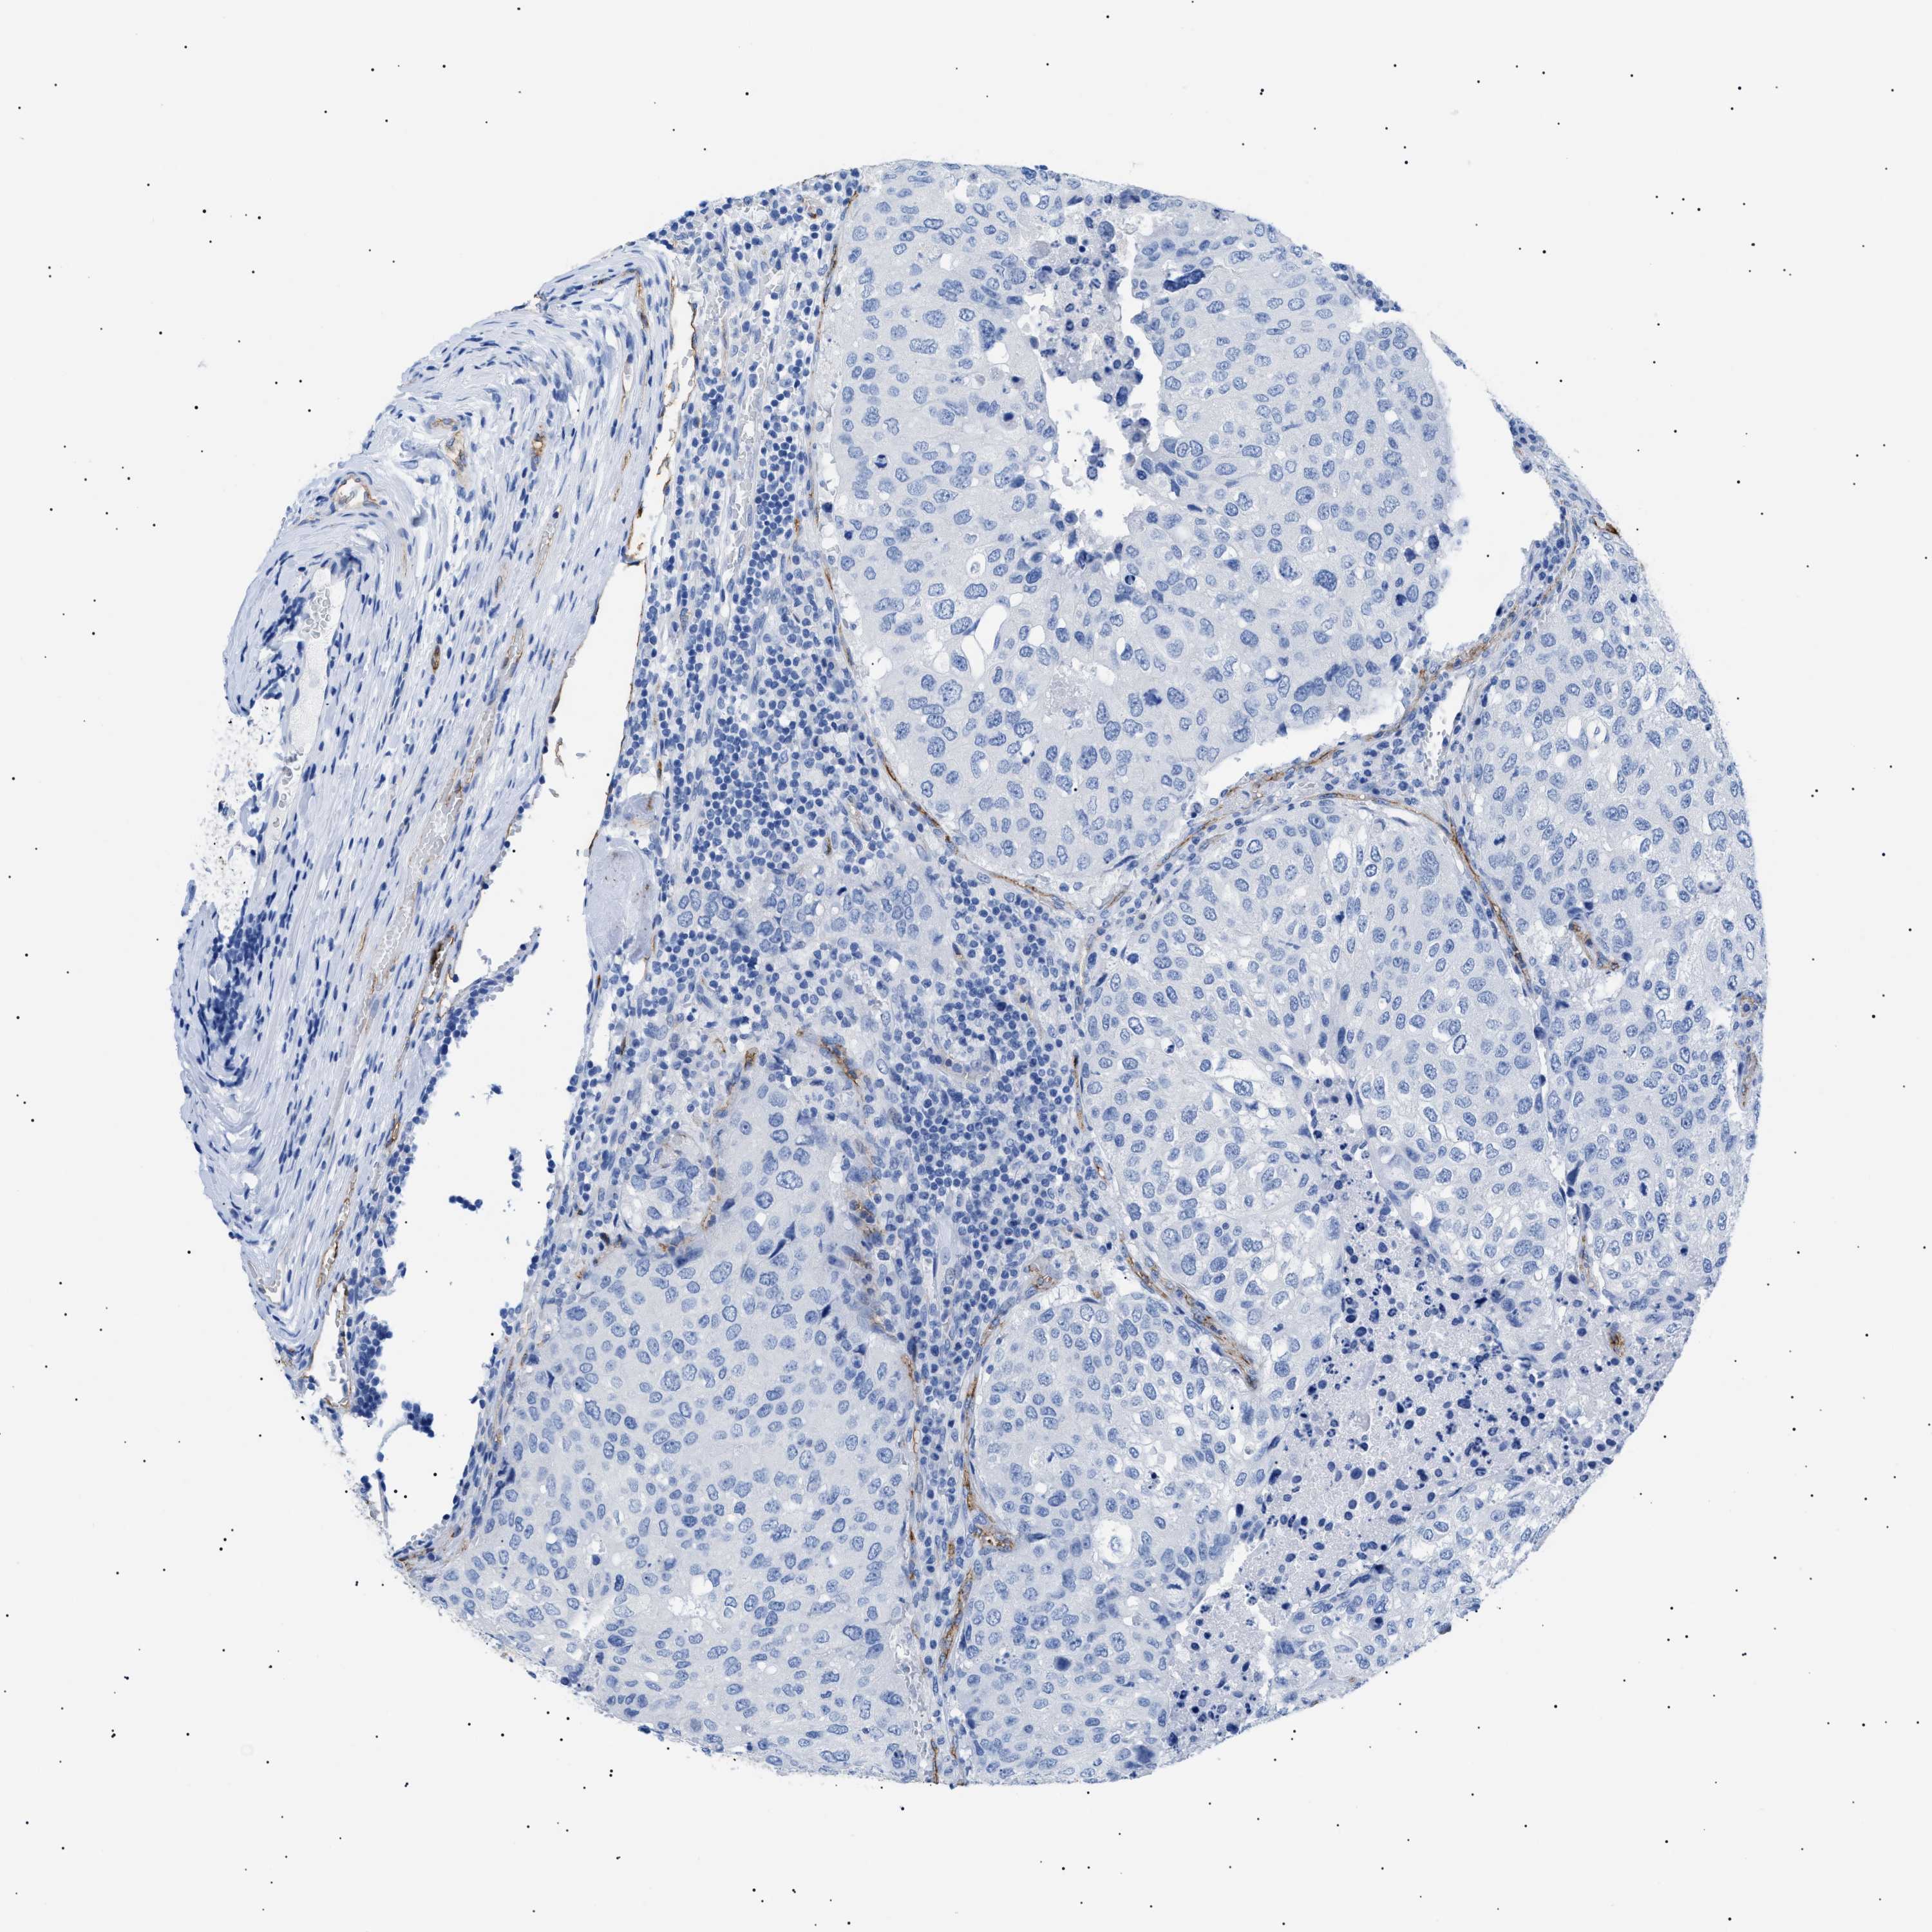

UROTHELIAL CANCER - Protein expressioni

A mouse-over function shows sample information and annotation data. Click on an image to view it in a full screen mode. Samples can be filtered based on level of antibody staining by selecting one or several of the following categories: high, medium, low and not detected. The assay and annotation is described here.

Antibody stainingi

Antibody staining in the annotated cell types in the current human tissue is reported as not detected, low, medium, or high, based on conventional immunohistochemistry profiling in selected tissues. This score is based on the combination of the staining intensity and fraction of stained cells.

Each image is clickable and will lead to virtual microscopy that enables deeper exploration of all samples and also displays staining intensity scores, fraction scores and subcellular localization as well as patient and tissue information for each sample.

HPA002110

HPA045507

CAB016169

CAB062558

CAB068219

CAB068220

Staining

High

Medium

Low

Not detected

Intensity

Strong

Moderate

Weak

Negative

Quantity

>75%

75%-25%

<25%

None

Location

Nuclear

Cytoplasmic/membranous

Cytoplasmic/membranous,nuclear

Urothelial carcinoma, High grade

Urothelial carcinoma, NOS

Urothelial carcinoma, Low grade